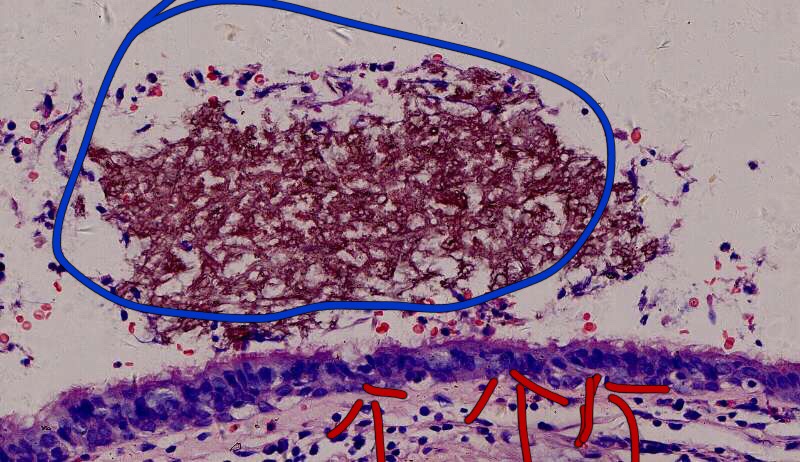

为什么有含铁血黄素呢? 曲霉菌容易使周围出现出血。太多含铁血黄素,吞不完 剩下一点曲霉菌,看看:

菌丝都快死了,隐约可见 这些红黑色点点是什么? 王:中性粒细胞,挺多的。这也是曲霉菌感染的一个特点。

曲霉菌孢子很少见到,基本都是菌丝团,这里也是支气管扩张区,菌丝团偏黄褐色,也快死了。

蓝色圈圈是菌丝团?红色箭头是淋巴细胞?这是空腔边缘吗?王:是的,红箭头也可能是中性粒细胞。 红箭是支气管粘膜有炎症。

这里的菌丝形态清楚,下图小圆空的结构挺多,我理解为管状菌丝的断面

3rd 在隔离肺的支气管里 也是在扩张的支气管内,有炎症细胞 紫红的可能是锰铁化,曲霉菌能吸收空气中的锰铁元素,在周边